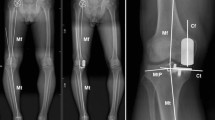

Definition of lower limb alignments and boundary conditions

The hip-knee-ankle line defines the position of the mechanical axis, which needs to be measured in the anterior-posterior projection and in full-length standing X-rays. It is considered the gold standard for measuring the lower limb alignment as it accurately measures the mechanical tibiofemoral angle and assesses limb deformities. The mechanical axis of the lower limb, also known as the Mikulicz line, is drawn by connecting a point at the center of the femoral head to a point at the center of the ankle. The physiological position of this line is on average 4 ± 2 mm medial to the center of the knee. Any deviation from this physiological range, such as an outward extension of the line, is called varus, and if the line extends inward, it is called valgus. The deviation value is measured in millimeters and is referred to as the mechanical axis deviation (MAD)19. In this experiment, starting from the midpoint of the knee joint and directed toward the medial side of the knee joint, points were marked at 1 mm intervals to simulate the Mikulicz line passing through different points of the knee joint, resulting in a total of 60 different finite element models of the knee joint. The medial side was recorded as + MAD, and the lateral side was recorded as -MAD. The tibia was fixed, and the coordinates XYZ and -X-Y-Z of the distal fibula were constrained while the femur was defined as a solid entity. A remote point and remote force were set, coupling all nodes on the surface of the femur. The remote point was set at the center of the femoral head, and the remote force was directed vertically downward with a load of 1000 N to simulate a complete biomechanical analysis on a complete knee joint20,21. The finite element model was subsequently modified sequentially to ensure the accuracy of the experiment and to minimize deviations. Throughout the entire experimental process, except for the different lower limb alignments, all other load conditions and parameter settings remained consistent (Fig. 3: Generated using Ansys 2021 R1 (Ansys, Inc., Canonsburg, Pennsylvania, United States))

ROI setting: To quantitatively evaluate the maximum principal strain/limit of elastic strain within the bone, we defined four regions of interest (ROI) on the inner side of the proximal tibia. ROI 1 is located on the innermost side of the proximal tibia, and ROI 2–4 are sequentially positioned outward with a spacing of 12 mm. ROI 4 is located on the outer side slightly away from the center of the knee joint (Fig. 3: Generated using Ansys 2021 R1 (Ansys, Inc., Canonsburg, Pennsylvania, United States))